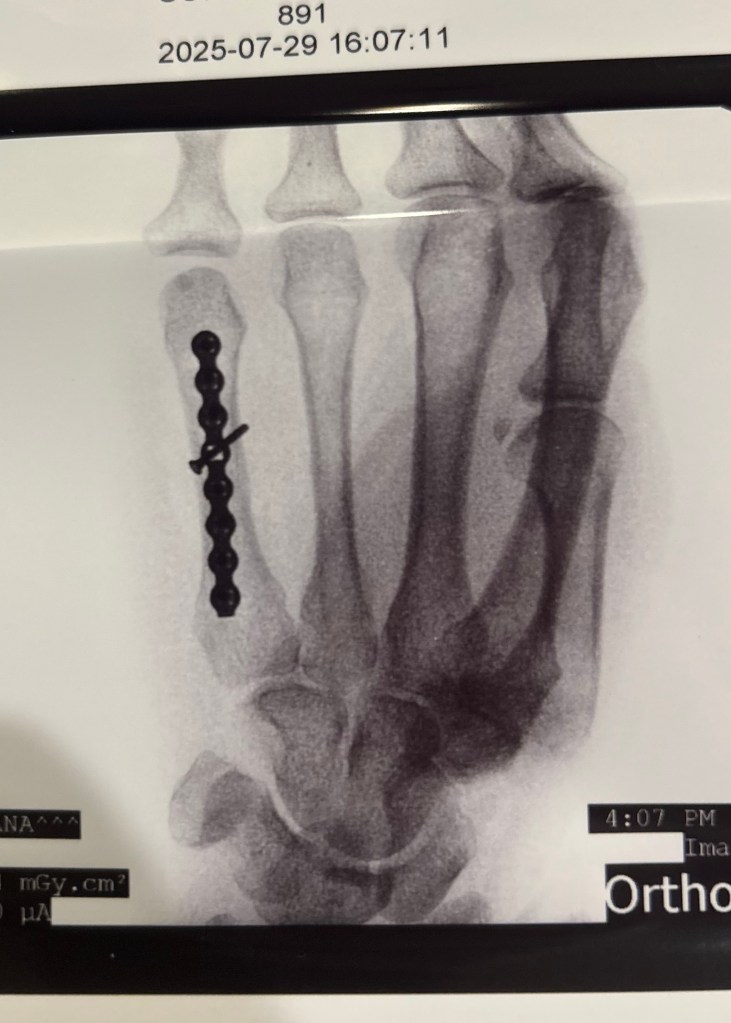

Yup, that was a real fall.

Nothing a plate and a few screws couldn’t fix.